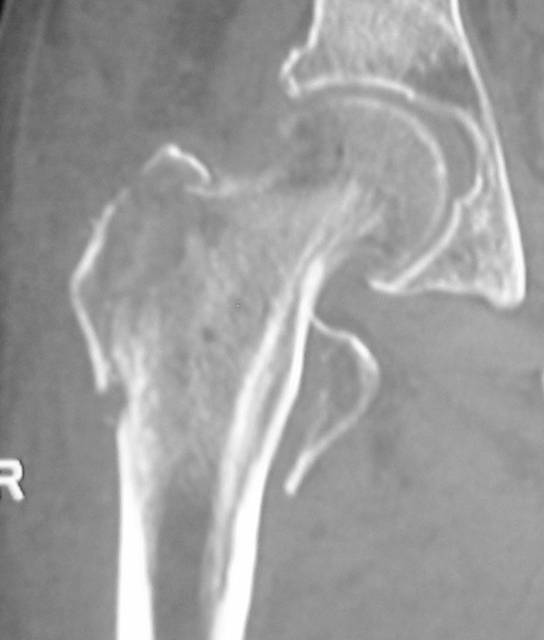

Radiography of the hip demonstrated avulsion of the lesser trochanter and fracture of the greater trochanter with no apparent intertrochanteric extension (Fig. 1). The fracture condition was well revealed by the CT scan (Fig. 2). MRI showed no typical abnormality at the intertrochanteric lesion (Fig. 3). Laboratory data including full blood cell count were normal. NTX/CR was normal. DEXA scan of vertebral bones showed a bone density 0.925 g/cm2, which is 88% of the means Japanese young adults.

Fig. 2 Reconstructed CT scan of right hip showing isolated fractures of the greater and lesser trochanter